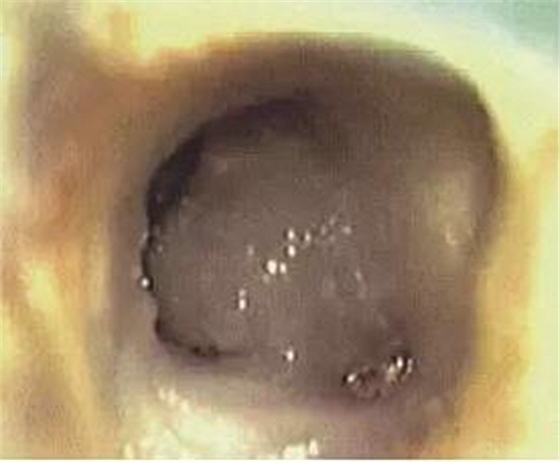

常規(guī)開(kāi)髓后可在顯微鏡下看到髓室底有C形根管形態(tài),或呈C形(圖1),或呈分號(hào)形(圖2)。參考上期所涉及的C形根管分類圖進(jìn)行診斷。

圖1 髓室底根管口呈C形